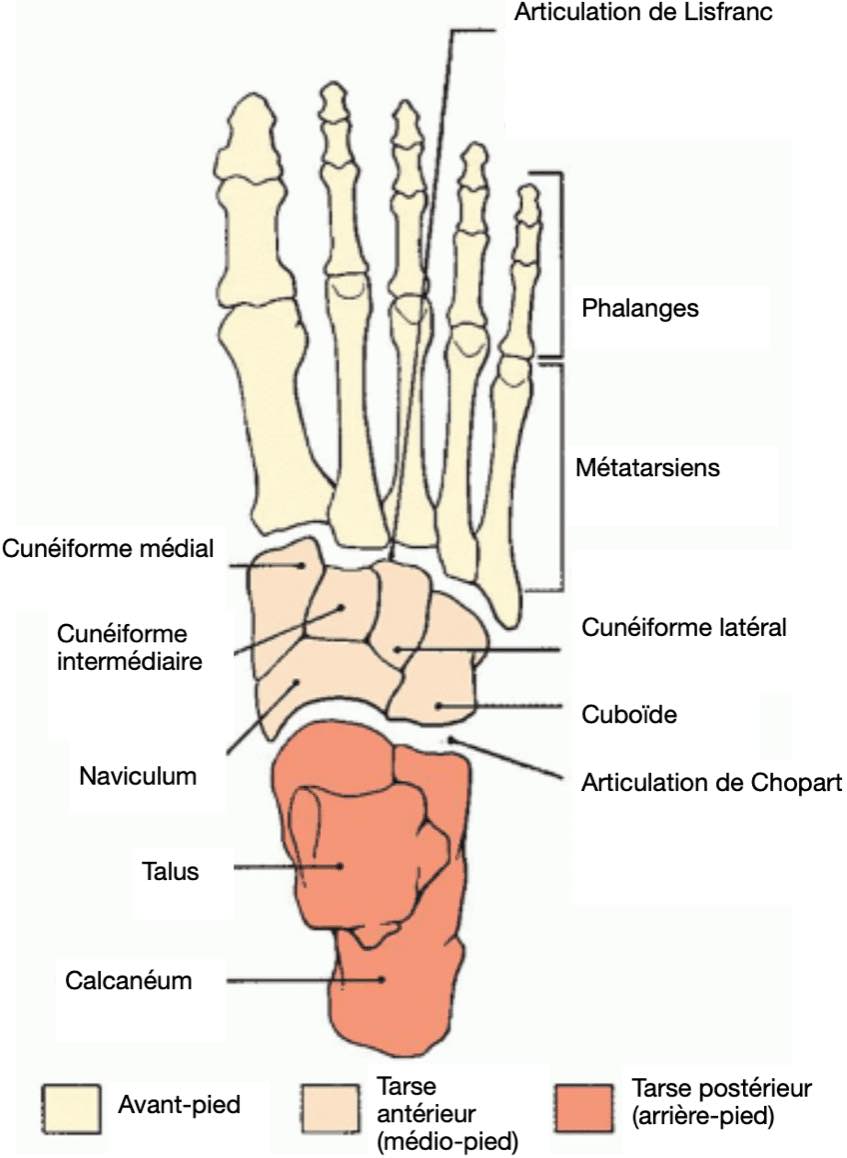

Respect des interlignes articulaires du tarse, métacarpophallangiennes et interphallangiennes.

Pas d'érosion osseuse ni de lésion suspecte.

Pas de lésion post-traumatique récente.

Parties molles sans particularité.

Entorse

Pas d'épanchement dans l'articulation tibio-talienne.

Aspect normal des ligaments talofibulaire antérieur et calcanéofibulaire.

Respect des ligaments talonaviculaire dorsale, tibiofibulaire antéro-inférieur et calcanéocuboïdien latéral.

Comblement graisseux hyperéchogène sans particularité du sinus du tarse.

Tendons court et long fibulaires en place, sans épanchement.

Talalgies

Respect de l'échostructure des aponévroses plantaires, sans épaississement.